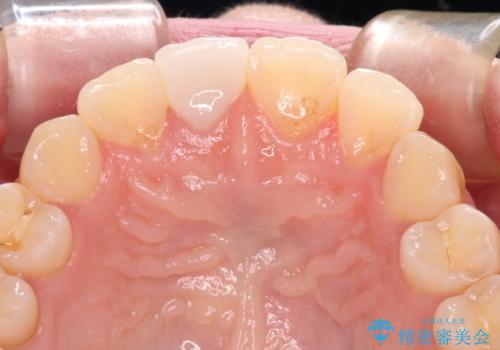

転んで前歯の先端1/3ほどが欠けており、近医にて応急処置としてコンポジットレジン修復がされていました。

審美性や舌触り、今後の歯への負担などを考え、オールセラミッククラウンにて補綴治療を行うこととしました。